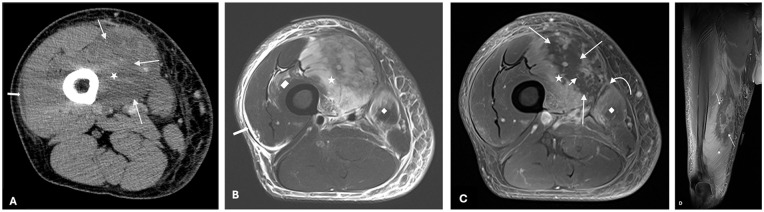

Diabetic myonecrosis is a rare complication of poorly controlled diabetes that presents as spontaneous limb pain and swelling. It is associated with other microvascular diabetic complications such as nephropathy or retinopathy and is frequently misdiagnosed given its resemblance to infectious and vascular complications. We present a case of a 49-year-old male with poorly controlled type 2 diabetes and a history of recurrent thigh pain. This was initially treated as cellulitis, but the patient experienced persistent severe pain despite multiple rounds of antibiotics. Imaging with MRI ultimately confirmed a diagnosis of diabetic myonecrosis. The patient was successfully managed with a combination of aspirin, insulin therapy, and a multimodal pain regimen, leading to significant clinical improvement. This condition poses a diagnostic challenge due to its rarity and nonspecific presentation, often leading to delays in appropriate treatment. Prompt diagnosis with exclusionary testing and imaging, followed by appropriate management, can prevent severe complications. Additional research is needed to establish a standardized protocol for treating this condition.

Abstract Image